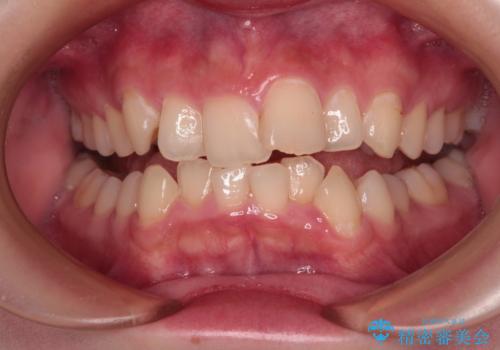

- 上下前歯のねじれを気にして来院された患者様です。

ワイヤー矯正でもマウスピース矯正でも対応可能でしたが、マウスピース矯正の自己管理が面倒であること、上顎前歯の捻転が著しいことから、ワイヤー矯正での治療を希望されました。

日々前歯の捻れが解消されていくので、歯の動きを楽しみながら矯正治療を進めることができました。